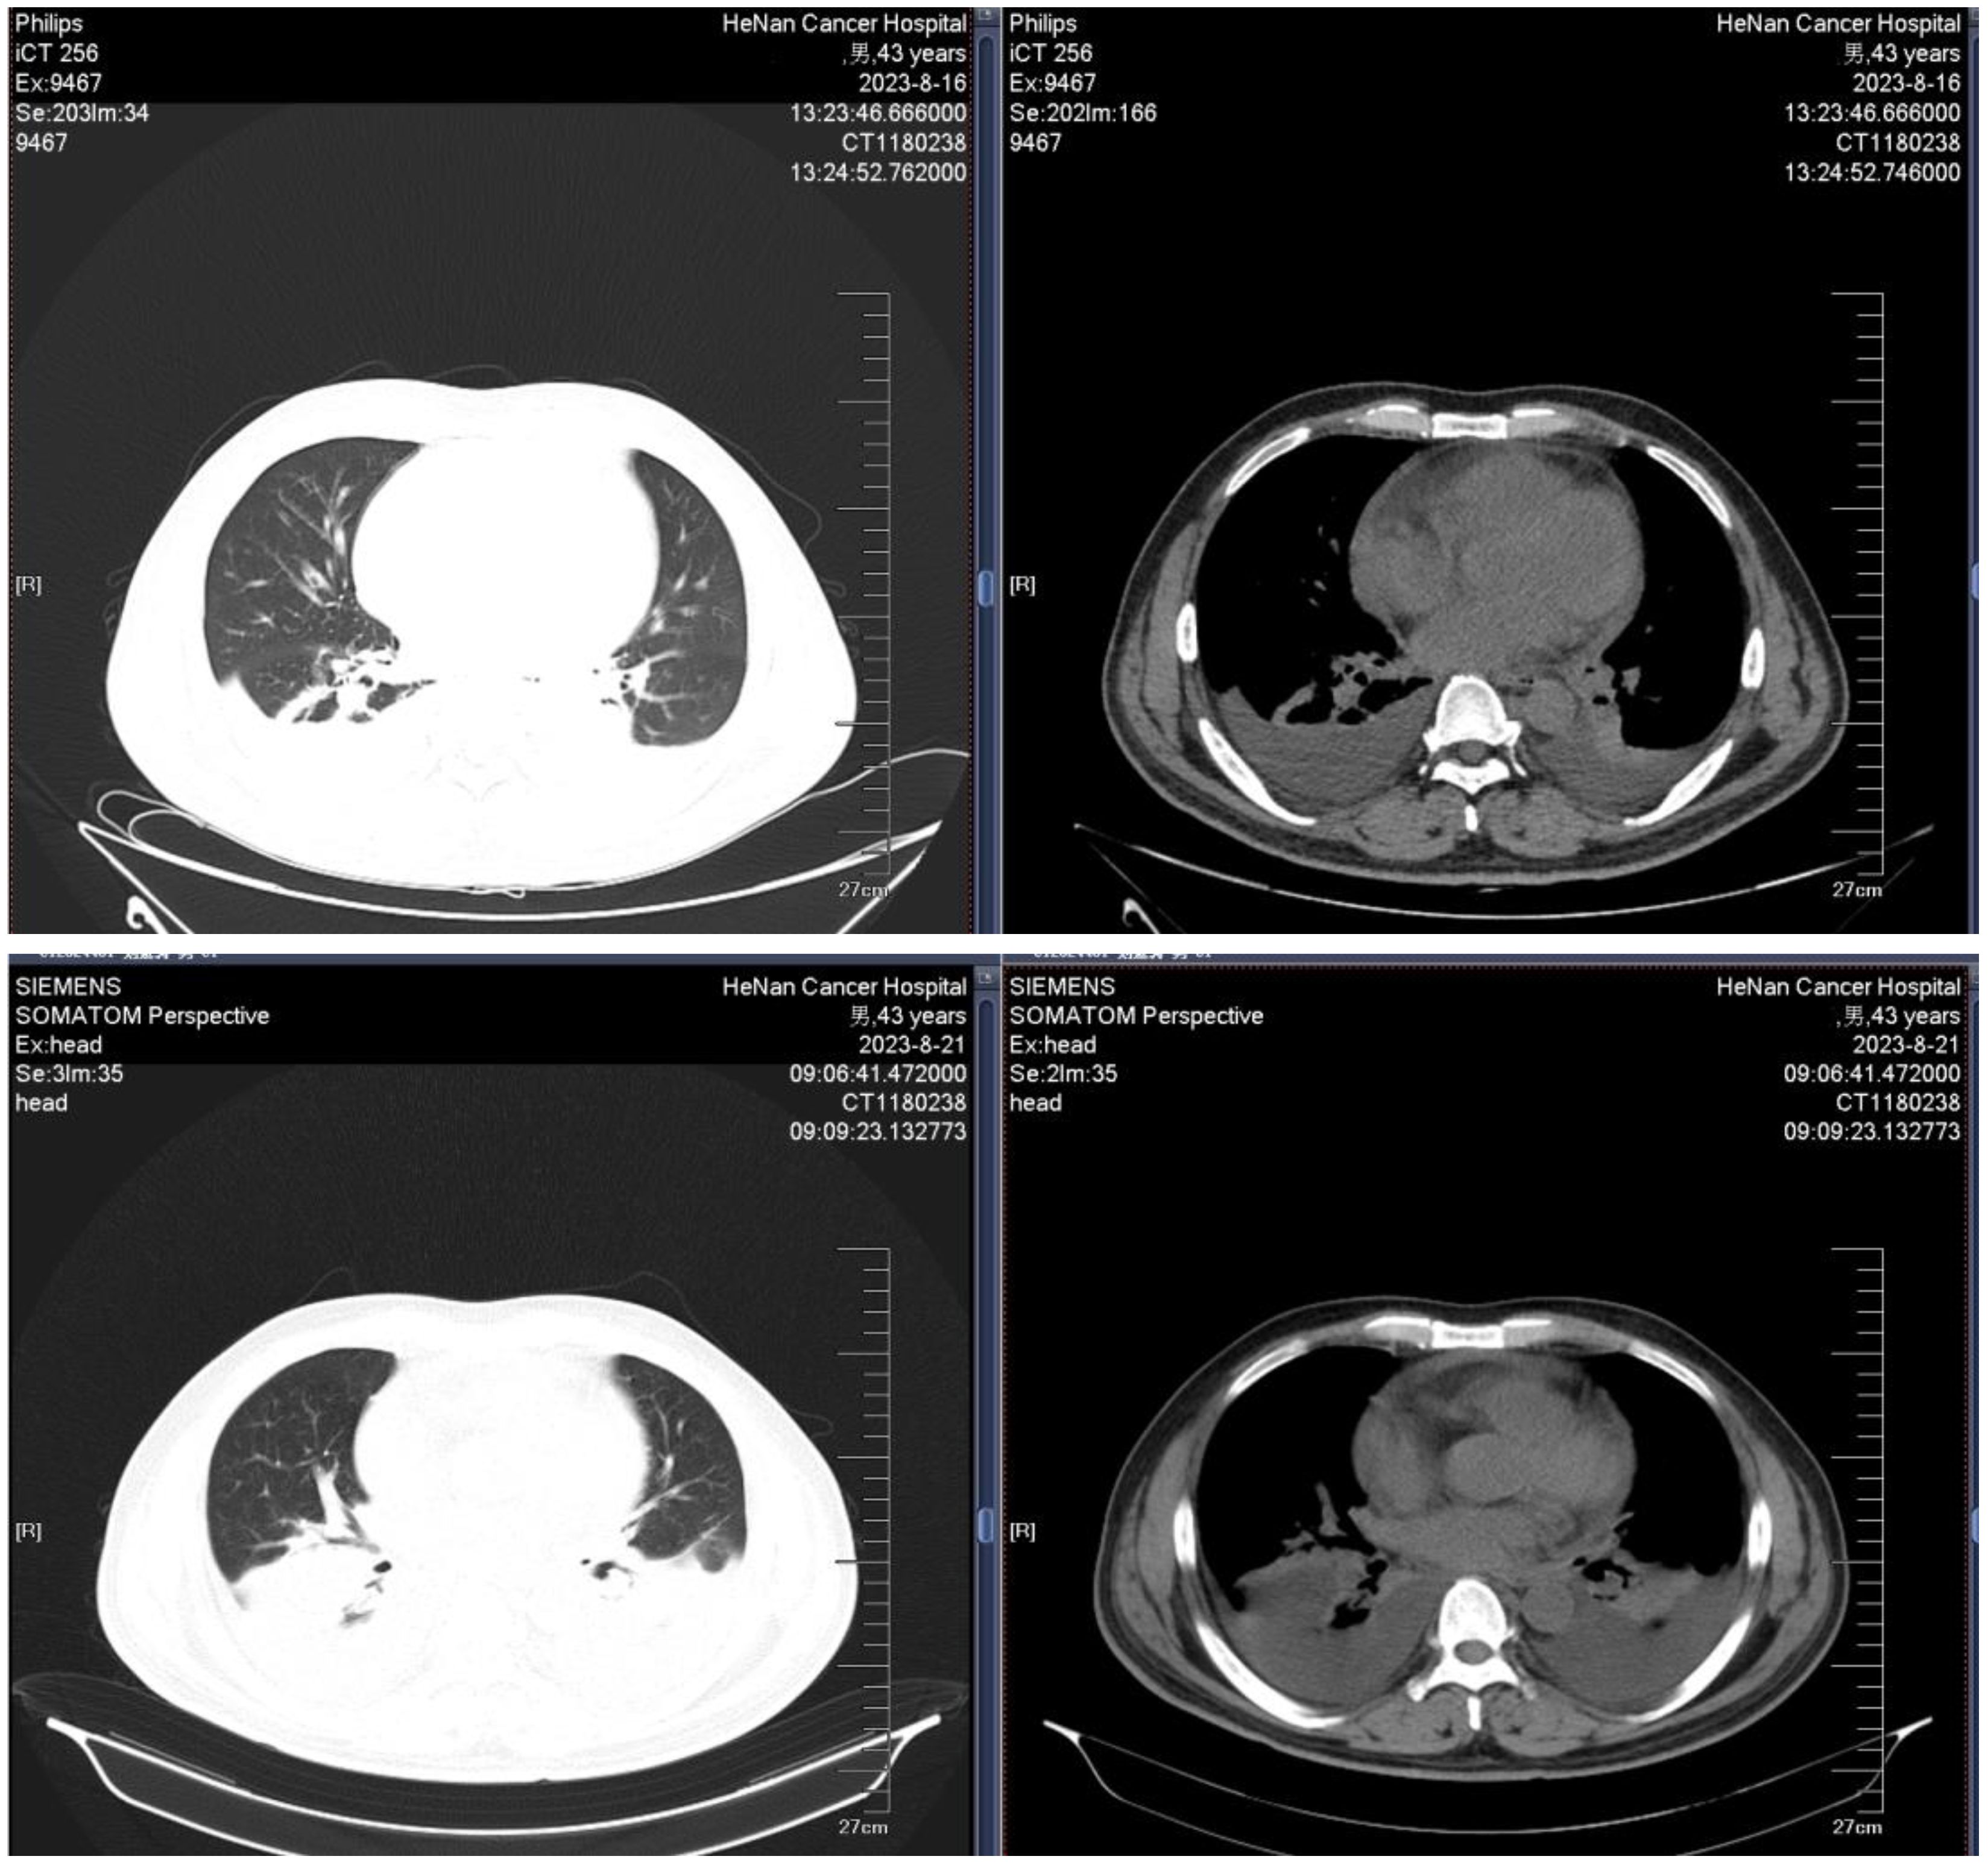

A 43-year-old male was admitted to the hospital owing to fatigue on July 14, 2023. Analysis of the complete blood count revealed the following: white blood cell (WBC) count, 94.48×109/L; hemoglobin (HGB) level, 67 g/L; platelet (PLT) count, 151 ×109/L; and neutrophil count (N#), 0.95 × 109/L. Analysis of the morphology of cells in a peripheral blood sample revealed that blast cells accounted for 85% of the total cells. Analysis of the morphology of the cells in a bone marrow (BM) sample revealed that proliferation was extremely active, with blasts accounting for 87.2% of the cells. BM immunophenotyping revealed that abnormal blasts accounted for 79.83% of the immune cells, which expressed HLA-DR, CD117, CD38, CD33, CD15, CD7, CD123, and cCD3 and weakly expressed CD3, CD13, CD56, CD2, CD64, cMPO, and CD11c. Karyotype analysis revealed a normal male chromosome pattern (46, XY)[20]. Next-generation sequencing (NGS) revealed mutations in CEBPA, NQO1, TNFAIP3, EZH2, KMT2D, and SETD2 and high expression of BCL-2, and no abnormal fusion gene was found. The patient was definitively diagnosed with T/myeloid MPAL. All diagnoses were made in accordance with the Chinese guidelines for the diagnosis and treatment of adult acute lymphoblastic leukemia (2021). The patient was infected with severe acute respiratory syndrome coronavirus 2 (SARS-CoV-2) and had a persistently high body temperature and severe lung infection, and his basic condition was poor. Since the patient was not eligible for receiving standard induction regimens, the VA regimen (ven 100 mg d1, 200 mg d2, 400 mg d3~28, azacitidine 100 mg, d1~7) was given to the patient on July 27, 2023, to induce remission. Analysis of the morphology of cells in a BM sample obtained after 15 days of treatment revealed 10.5% blast cells and measurable residual disease (MRD) detected by multiparameter flow cytometry (FCM), with 4.9% abnormal blasts (FCM analysis for all MRD assessments in this study was performed using the standardized 10-color panels with a sensitivity threshold of 0.01%). During treatment, the patient experienced complications such as a persistently high body temperature, severe lung infection, and pleural effusion (some images from the chest CT examination are shown in Figure 1). Morphological examination of a BM sample obtained on day 29 suggested CR. An analysis of MRD revealed no abnormal blast cells. Genetic testing revealed no mutations in the CEBPA gene. The first cycle of myelosuppression lasted 26 days. The changes in the hemogram are shown in Figure 2. The patient subsequently received 1 cycle of the VA regimen consolidation treatment again. After remission, the patient underwent lumbar puncture + sheath injection treatment and subsequently underwent matched sibling donor allo-HSCT. Unfortunately, the patient died of multiorgan failure due to capillary leak syndrome 2 days after transplantation.